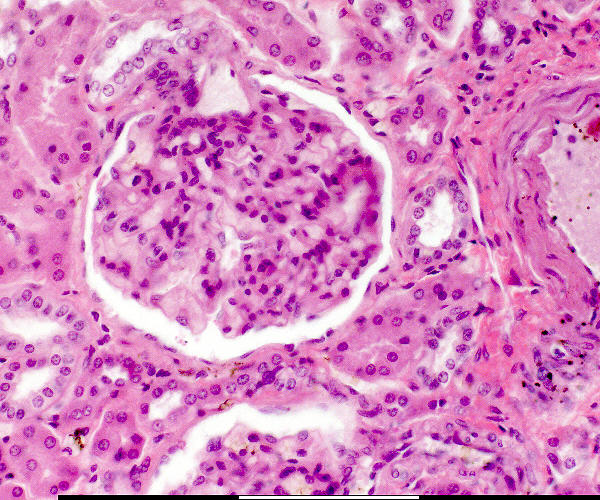

Bloedvat / Blood vessel

Versamelbuis / Collecting tubule

Makula densa / Macula densa

Pariëtale selle / Parietal cells

Pariëtale laag / Parietal layer

Podosiete / Podocytes

Urinêre spasie / Urinary space

Vaskulêre pool / Vascular pole

Visserale laag / Visceral layer

Jukstaglomerulêre apparaat / Juxtaglomerular apparatus